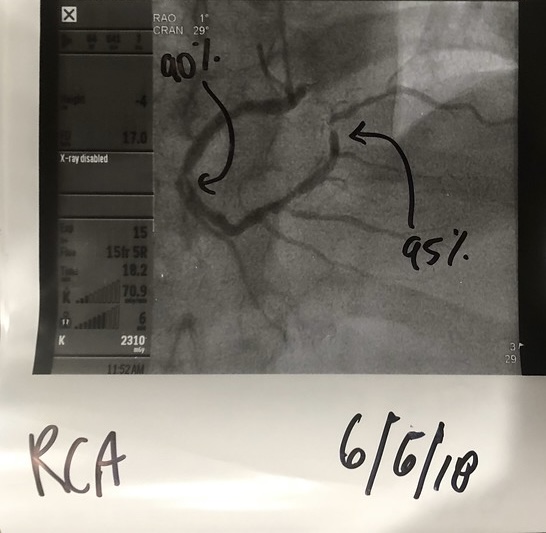

Surgeon wants to put in a couple of stents and look around to see what else he can fix....